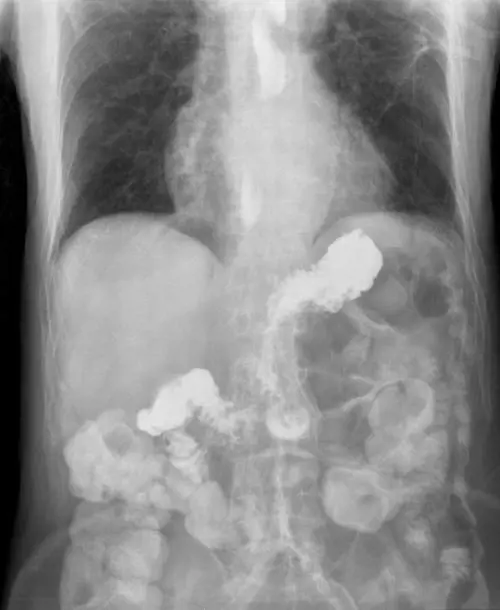

Ingoia monete per scherzo ma finisce per trascorrere due giorni in ospedale: un trucco di magia finito male che ha rischiato di avere conseguenze gravi sulla salute